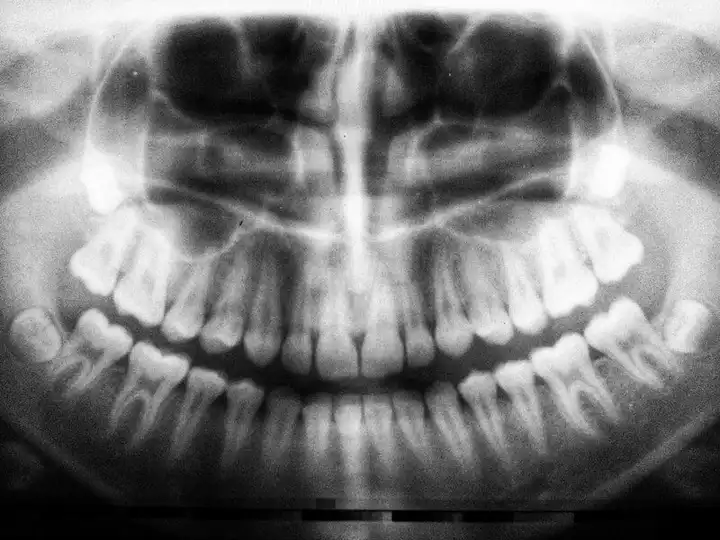

Your dentist and hygienist use dental X-rays to see areas of your mouth that aren’t visible. Are they safe? Yes, modern digital X-rays are safe.Dental X-rays While Pregnant - Are They Safe?

Thanks to today’s low-radiation digital X-rays while pregnant and ALARA, you and your child will be completely safe if dental radiographs are needed.